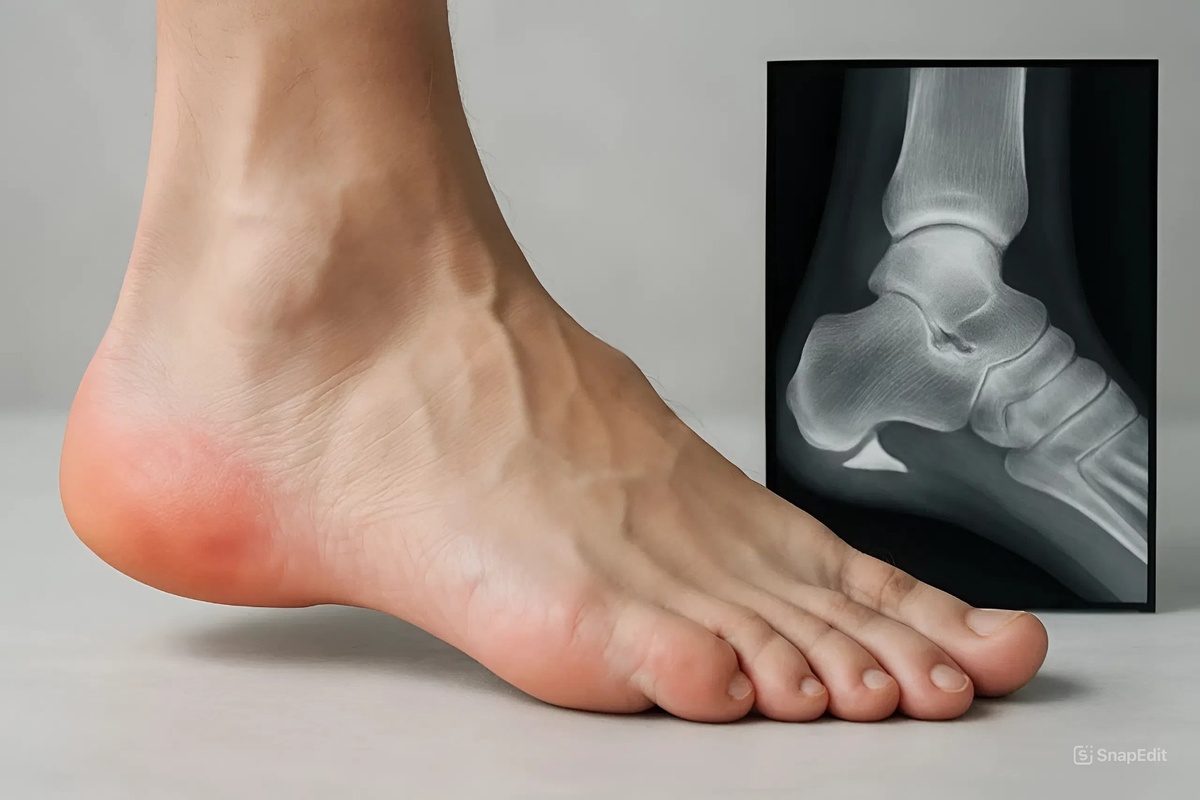

Боль в пятке при наступании по утрам в 90% случаев — это плантарный фасциит, который в народе называют "пяточной шпорой".

Фасция — это плотная соединительнотканная пластина на подошве, которая идёт от пяточной кости к основаниям пальцев. Она работает как амортизатор и поддерживает свод стопы.

Когда фасция воспаляется и утолщается, возникает боль. А костный вырост (шпора) на пятке — это не причина, а следствие длительного воспаления. Шпора появляется там, где фасция тянет надкостницу, и организм «укрепляет» это место кальцием.

❓ Нужно ли делать рентген?

Рентген покажет шпору, если она есть, но для диагноза он не обязателен. Диагноз «плантарный фасциит» ставится на основе жалоб и осмотра. Рентген нужен, чтобы исключить перелом или другое заболевание кости. В большинстве случаев достаточно осмотра врача.